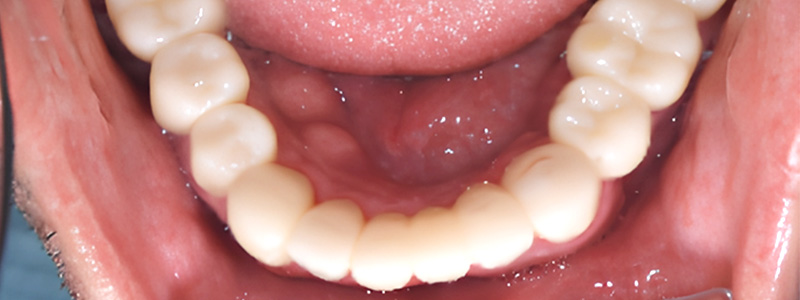

- 治療名

- オーバーデンチャー

- 治療内容

- 残存歯のむし歯治療・入れ歯治療

- 患者様

- 50代男性

- 治療期間

- 4ヶ月

- 費用

- ¥1,067,000

- 治療に対するリスク

- 疼痛

- 執刀医

- Dr.村尾